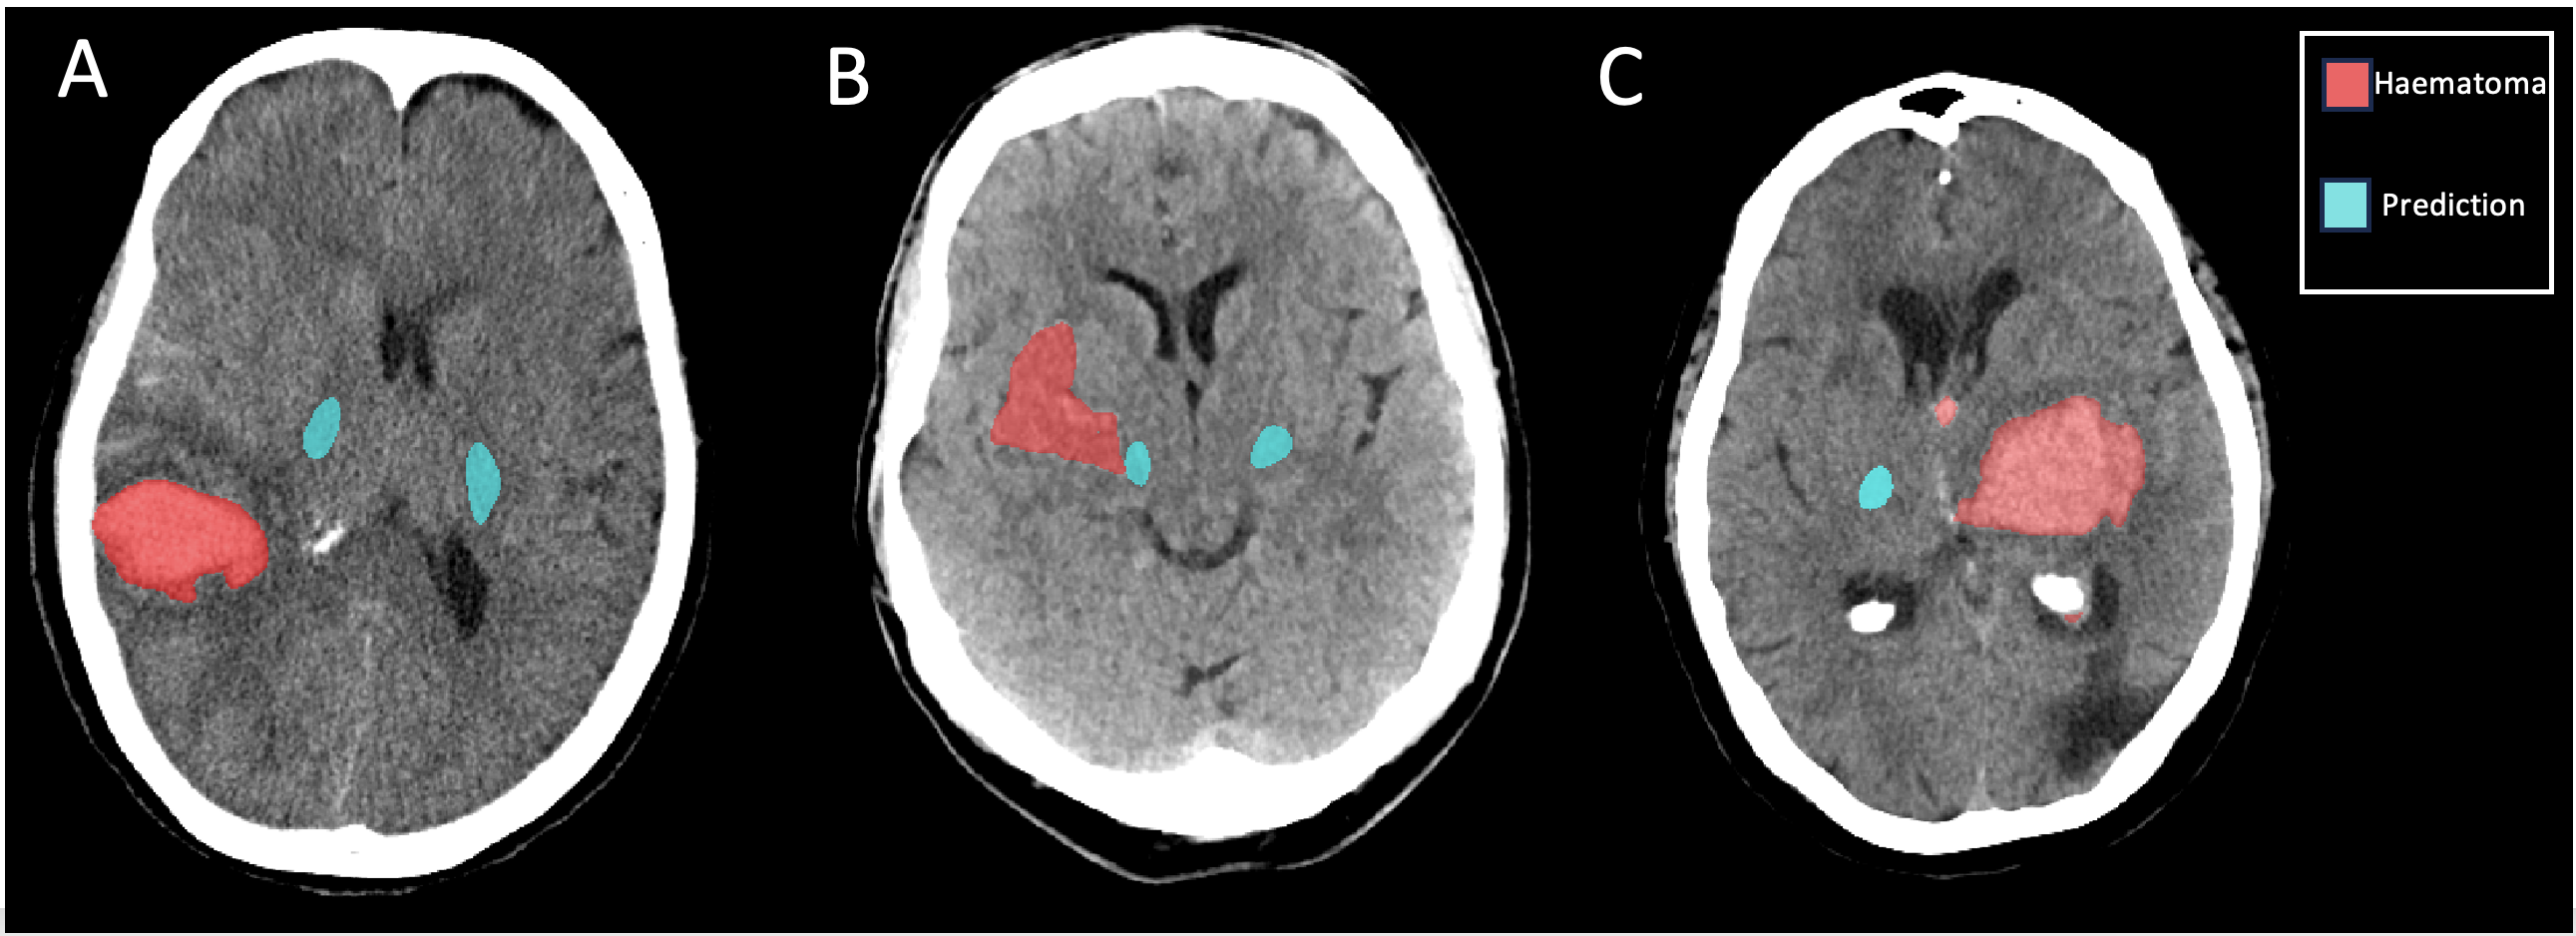

Inference was run over diagnostic CT scans from the MISTIE III clinical trial dataset, and predicted labels of the CST and haematoma were generated for 487 patients, three of whom are shown in Figure 3. Demographics of the MISTIE III trial, split by CST integrity, are described in Table 1.

Refer to caption

Figure 3: Three patients from the MISTIE III dataset with predicted CST and haematoma labels. A) A patient with a haematoma not involving the CST B) A patient with CST haematoma overlap but no split tract C) A patient with no CST haematoma overlap, but a split tract.